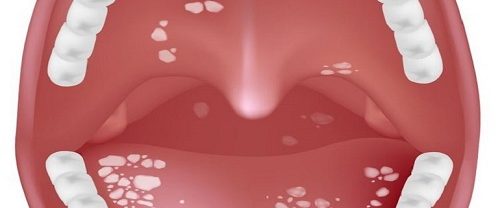

Uvulopalatoplasti Küçük Dil Kısaltılması Nedir? Uvulopalatoplasti Küçük Dil Kısaltılması, tıbbi bir prosedür olarak, genellikle horlama ve uyku apnesi gibi solunum problemlerini tedavi etmek için kullanılan bir cerrahi müdahaledir. Bu prosedürde, küçük dil ve yumuşak damakta değişiklikler yapılarak solunum yollarının açıklığı artırılmaya çalışılır. Küçük Dil ve Yumuşak Damak Anatomisi Öncelikle, küçük dil ve yumuşak damak yapılarını…